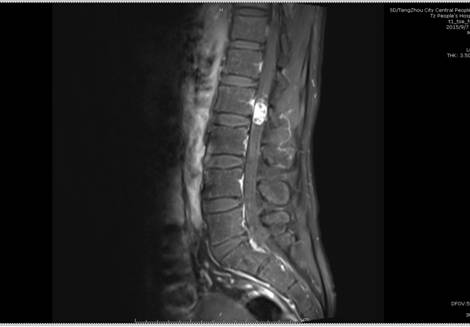

患者李某,男,40歲,因“右下肢疼痛、麻木8年余,伴腰部疼痛、活動受限1年余”入院,入院前患者曾在外院就診診斷為右側(cè)股骨頭壞死,一直予口服中藥治療,癥狀不見好轉(zhuǎn),近1月來癥狀明顯加重。來我院行腰部MRI檢查示L2椎體水平椎管內(nèi)占位,考慮良性神經(jīng)源性腫瘤;L5/S1椎間盤突出;腰椎退行性變。神經(jīng)外二科主任續(xù)繼軍帶領團隊仔細評估患者術前狀態(tài),多次進行病例討論,認為患者手術指征明確,但手術風險較大,容易引起下肢癱瘓、大小便失禁等并發(fā)癥?;颊哒登鄩涯辏瑸榧彝ブ兄е?,一旦喪失勞動力,對整個家庭將是災難性打擊。

術前影像學檢查